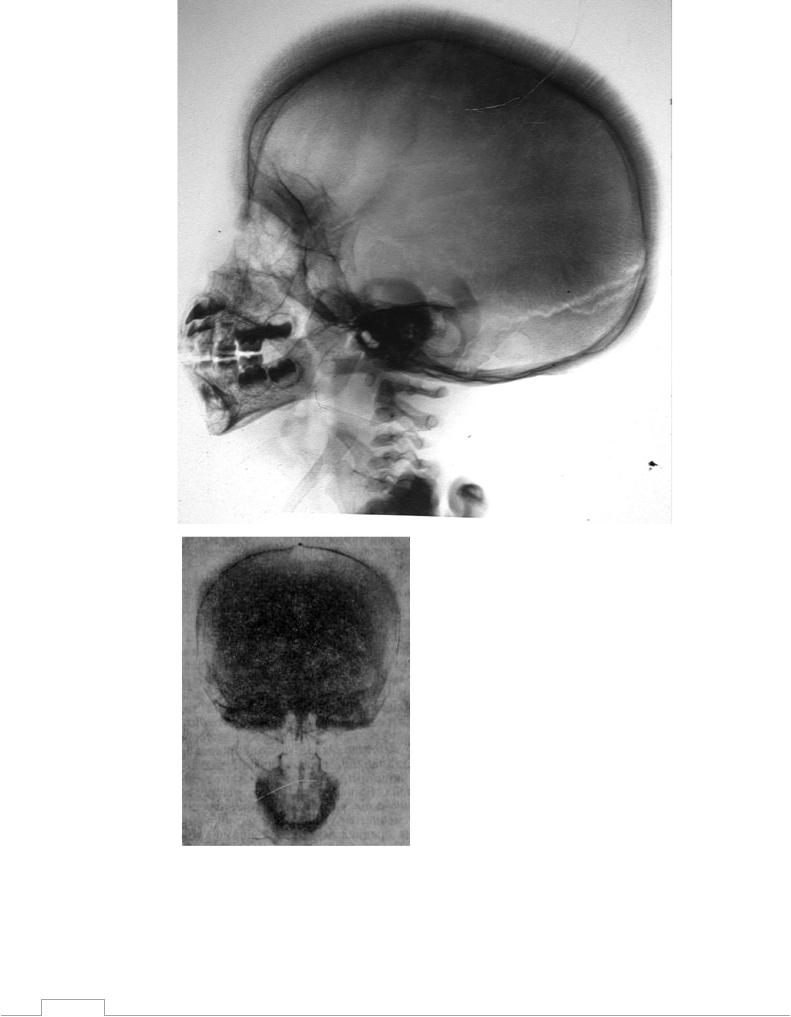

Рисунок 6. Рентгенограммы костей черепа больных талассемией. Отмечается характерная картина, называемая «Hair-on-end» (череп «щетка»), отражающая реакцию костной ткани на ее вовлечение в процесс формирования эритроцитов. Межкостное пространство расширено, костная ткань истончена, лицевой отдел черепа деформирован.